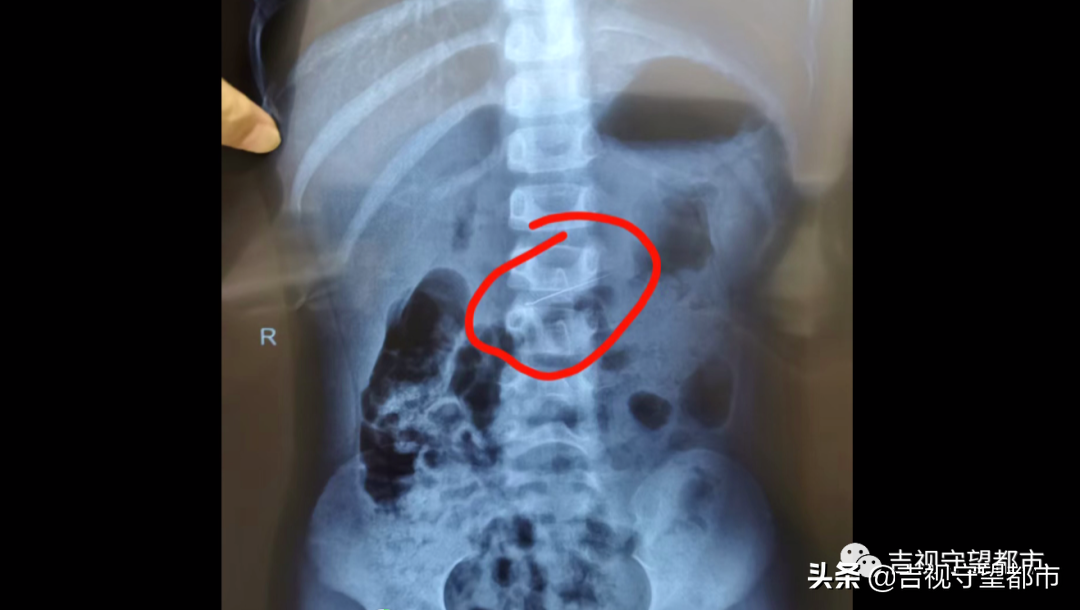

据家属描述,孩子误吞的这根修牙针长约4厘米,又细又尖,情况紧急,医生马上为患儿做了鼻咽镜,结果并未发现修牙针,怀疑针已经进入到消化系统。随即,院方马上为患儿安排拍片,最终在胃里发现了修牙针。